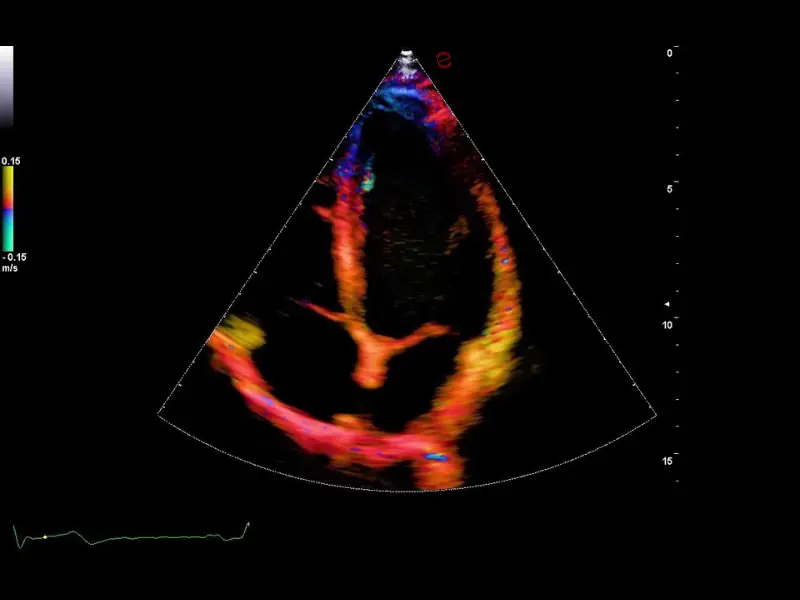

MyLab™9 Platform - Ultra-sensitivity Colour Doppler for precise visualization pulmonary veins

MyLab™9 Platform - Ultra-sensitivity Colour Doppler for precise visualization pulmonary veins